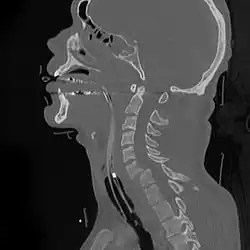

A fracture of the base of the dens (a part of C2) as seen on CT | |